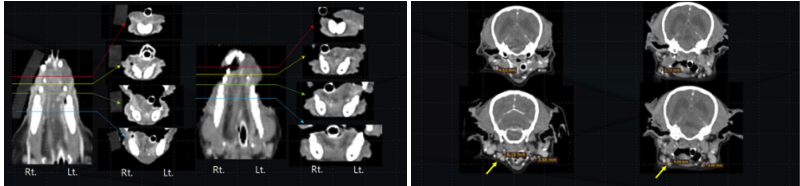

방사선 치료 후 결과 (4주 후)

치료 종료 후 4주 차에 종양 부위 리첵을 위해 CT 촬영을 진행하였으며, 다행히 재발이나 전이는 관찰되지 않았습니다. 또한 종양의 크기는 6mm에서 4.3mm로 감소하였습니다.

강아지 구강흑색종 (무색소성) 방사선치료 후 Recheck CT 결과 / 에스동물암센터